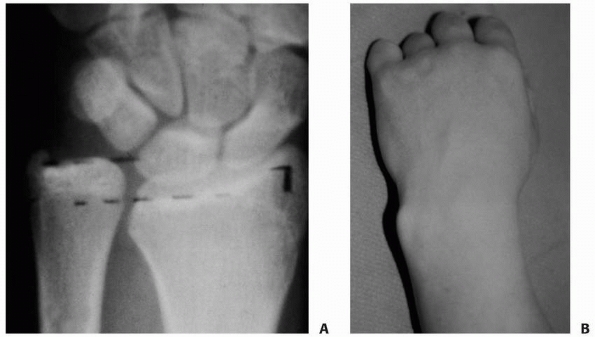

and angulation. Static AP and lateral radiographs can be diagnostic of

the fracture type and degree of deformity (Fig. 9-1). In adults,

the distal radial articular alignment averages 22 degrees on the AP view and 11 degrees on the lateral view.98,145,150,203,228

![]() |

|

FIGURE 9-1

Angulation of the x-ray beam tangential to the articular surface, providing the optimal lateral view of the distal radius. The wrist is positioned as for the standard lateral radiograph, but the x-ray beam is directed 15 degrees cephalad. (Redrawn from Johnson PG, Szabo RM. Angle measurements of the distal radius: a cadaver study. Skel Radiol 1993;22:243, with permission.) |